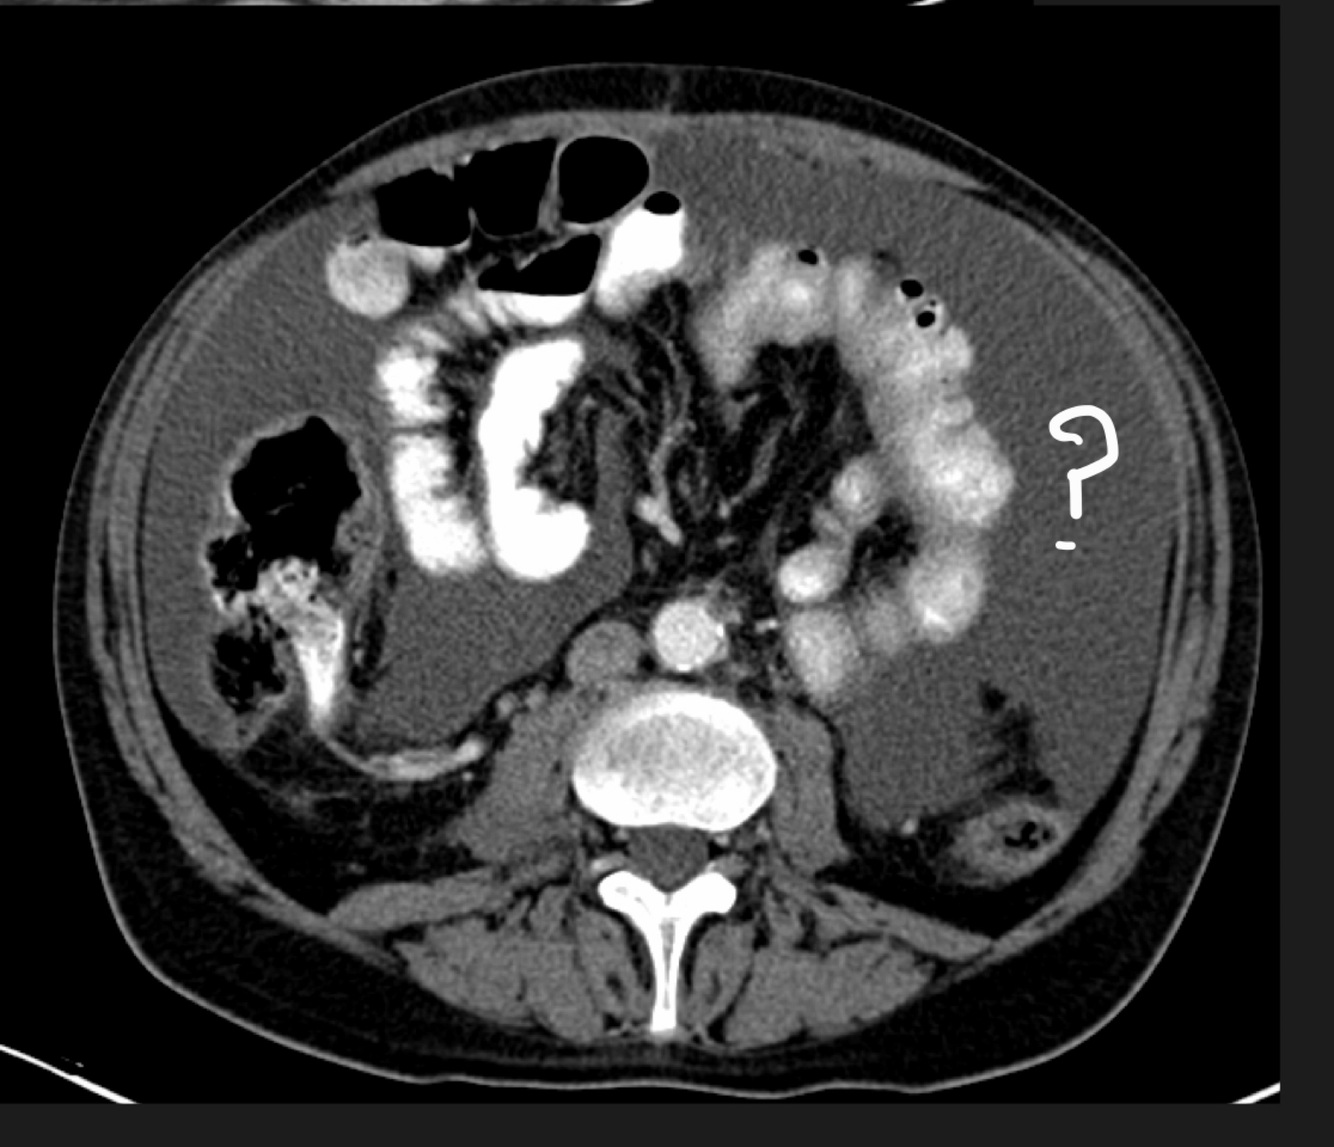

Name the marked structure

A

Ascending colon

How well did you know this?

1

Not at all

2

3

4

5

Perfectly

Q

1. Descending colon

2. Mesentery